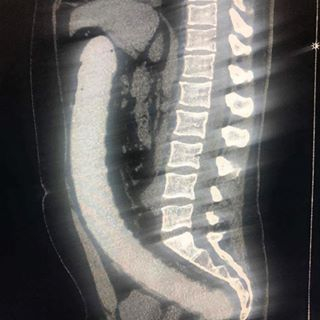

据统计,在急诊室中,男性“失物招领”的情况是女性的40倍,大部分失物是在肠道中被发现的,而且花样繁多……